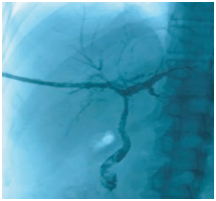

Figure 1 Cholangiography before BC removal. The intrahepatic bile ducts were poorly visualized, and patchy and tree-like negative shadows were seen.

BCs can prevent bile drainage, resulting in biliary obstruction and biliary tract infection. Percutaneous transhepatic cholangiography drainage is a common method for drainage of infected bile. After fistula extension, percutaneous transhepatic choledochoscopy can be implemented. We can observe the condition of the intrahepatic and extrahepatic bile ducts and remove multiple BCs with the help of choledochoscope, which is difficult by the conventional methods.19 In the process of removing BCs, we found that the BCs were shaped like the bile ducts, appearing as a hardened, dark material in the biliary ductal system with serious intrahepatic and extrahepatic bile duct injury. Some parts of the biliary mucosa showed patchy or strip defects, and mucosa ulcers were visible sometimes. After completely removing the BCs, the visualization of intrahepatic and extrahepatic bile ducts were improved, and patchy and bile duct mucosa were improved to varying degrees, showing reddish, smooth, rounded lumen and fresh bile secretion, and cholangiography displayed a very clear biliary tree (Figures 1–5).